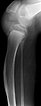

Seitliches Röntgenbild des linken Kniegelenkes mit Fehlwachstum von Ober- und Unterschenkel. Die Tibia hat in diesem Bereich im Wachstum eine Krümmung angenommen. Die Fibula steht dagegen gerade. Dennoch ist das wesentliche Problem auf das Kniegelenk beschränkt.

Dieser 12-jährige Patient mit PTEN-Hamartom-Tumor-Syndrom hat im Bereich seines Oberschenkels direkt über der Kniescheibe ein progredient wachsendes, schmerzhaftes PTEN-Hamartom entwickelt. Infolge von Schmerzen u. a. durch den mechanischen Druck bei Kniestreckung (Kniescheibe drückt gegen den Tumor) wurde zur Schmerzvermeidung stets eine Kniebeugehaltung eingenommen. Eine aktive Kniestreckung war im Verlauf auch durch das Fehlwachstum des Oberschenkelknochens nicht mehr möglich.

Zudem hatte der Patient eine Beinlängendifferenz mit einer Überlänge von ca. 3 cm des linken, betroffenen Beines.